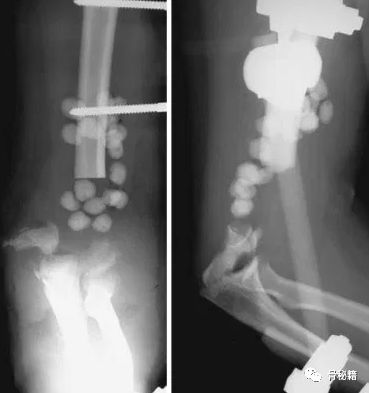

看看这些失败的case,肱骨远端不简单!

最难的最难的。。。灾难级的!当开放骨折+大量骨缺损遇到了感染你会怎么办?

30岁年轻男性

病例的结局

一期行外固定架+抗生素骨水泥控制感染,这个是常规的。

下一步?

二期同种异体肘关节移植术!并且将三头肌支点与原肘进行了重建

术后18个月,出现了失败和关节的不稳,但宿主和自体骨较好的结合了。

又进行了第二次肘移植,最后终于愈合